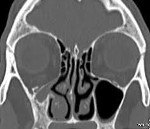

• КТ придаточных пазух носа. Компьютерная томография является «золотым стандартом» диагностики СМС. По ее результатам визуализируется одностороннее уменьшение внутренних размеров и затемнение гайморового синуса, компенсаторное увеличение объема глазницы. Также на снимках отображается крючковидная деформация боковой стенки пазухи, расширение ретроантральной жировой пластинки и среднего носового хода.